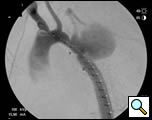

Selective angiography of the left subclavian artery was performed to confirm an intact posterior cerebral circulation. The proximal left subclavian artery was occluded with two 10mm Amplatzer vascular plugs which were introduced via the left external iliac sheath. An angiogram of the distal aortic arch and descending thoracic aorta was then performed to obtain a roadmap of the proximal and distal landing zones (Figure 4).